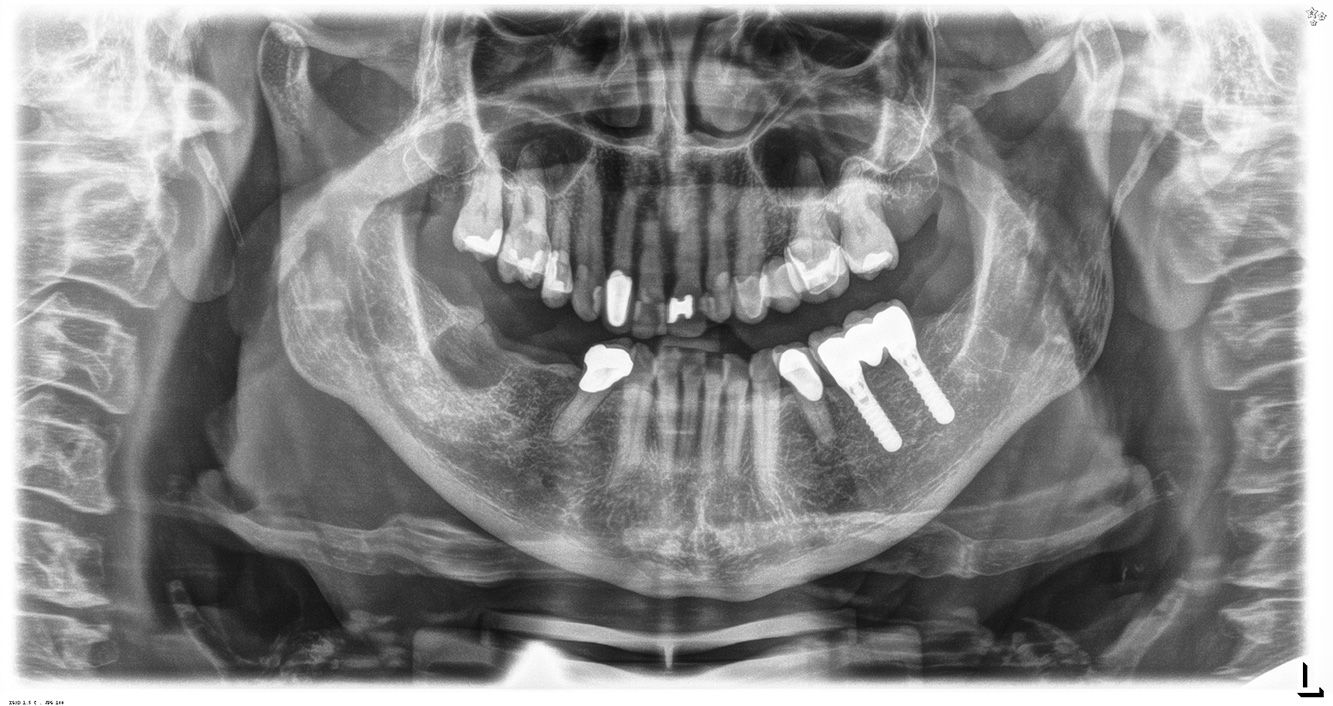

Der (mund)-gesunde Patient mit Implantaten

Der 55-jährige Patient gibt in der Anamnese an, keine Allgemeinerkrankungen zu haben und keine Medikamente einzunehmen. Die Lebensgewohnheiten des Patienten sind ebenfalls unauffällig. Der Patient hat einige zahnärztliche Restaurationen und zwei Implantate (2. und 4. Quadrant). Anhand der aktuellen Befunde lässt sich eine Gingivitis bei stabilem parodontalen Zustand am reduzierten Parodont (Stadium III, Grad A) feststellen. mehr Infos